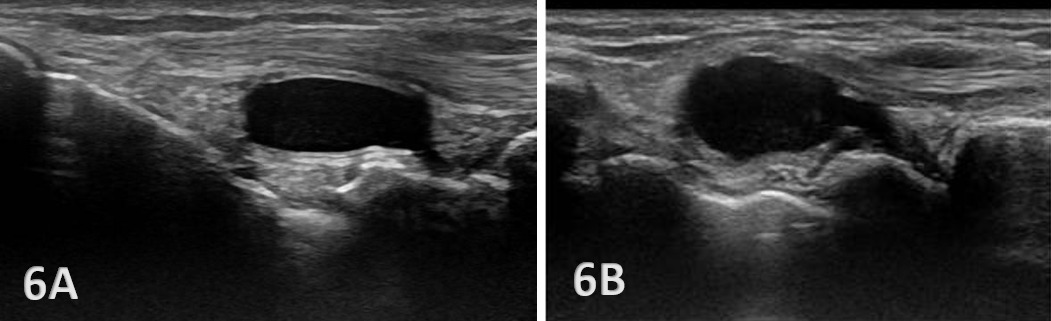

Anechoic or hypoechoic joint effusion and/or synovitis (synovial hypertrophy) and cysts within the joint.

Joint effusion is somewhat compressible and mobile when transducer pressure is applied to the area. This is different from synovitis, which appears as hypoechoic or isoechoic, non-compressible tissue within the joint recess. Synovitis may be associated with conditions such as rheumatoid arthritis, psoriatic arthritis, or other inflammatory arthropathies. Lastly, a ganglion cyst may appear as a well-defined, round or lobulated cystic structure with anechoic or hypoechoic internal contents. The cyst will usually have a small, smooth wall and exhibit posterior acoustic enhancement. These cysts will typically be minimally or non-compressible and painful.

Dynamic Functional Testing: Rehabilitation professionals can use MSKUS to dynamically stress the tissues with gentle wrist motion to reveal instability or soft tissue impingement between bones or abnormal findings such as cysts.

Guided Interventions: Ultrasound imaging assists in dry needling and precision-guided injections, such as corticosteroids for inflammation or treatment for ganglion cysts.5